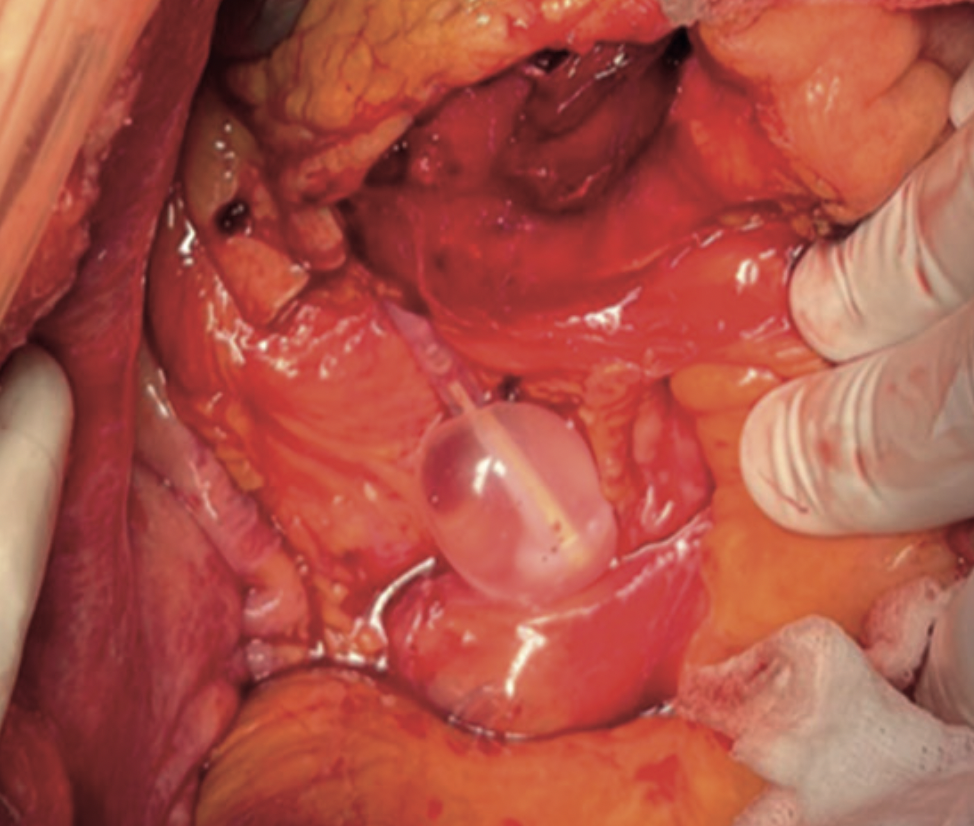

Se presenta el caso de una mujer de 83 años que acude al servicio de Urgencias con clínica de obstrucción inestinal secundaria a neoplasia de colon ascendente, que se interviene de forma urgente evidenciándose intraoperatoriamente perforación ureteral por sondaje vesical traumático.